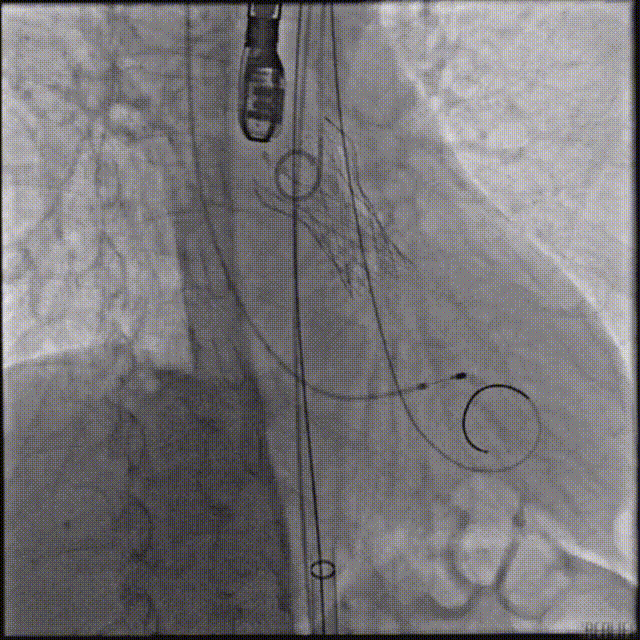

TaurusElite输送系统轻松过弓、跨瓣,AV23瓣膜瓣环上约2-4mm释放。

瓣膜初始位置释放

回收再定位释放

第一次释放到工作位后瓣膜下滑,回收调整位置后选择高位再次释放,最终造影显示瓣膜形态、位置良好,冠脉血流灌注正常,超声提示少量瓣周漏。